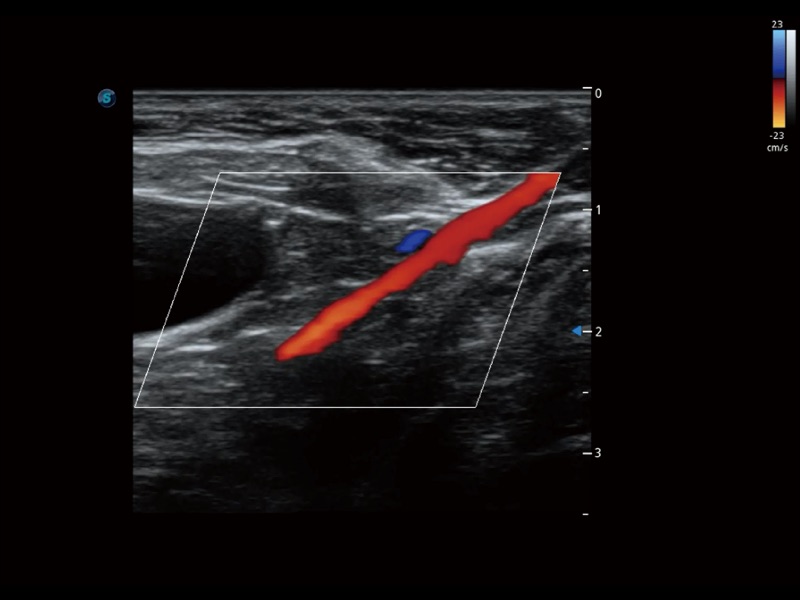

增强穿刺针在动物解剖结构中的位置,提高穿刺介入的安全性和准确性。

为精细结构及组织边缘提供高清晰度的图像和更大的成像视野。帮助减轻医生的用眼疲劳,快速精准获得测量的数据。